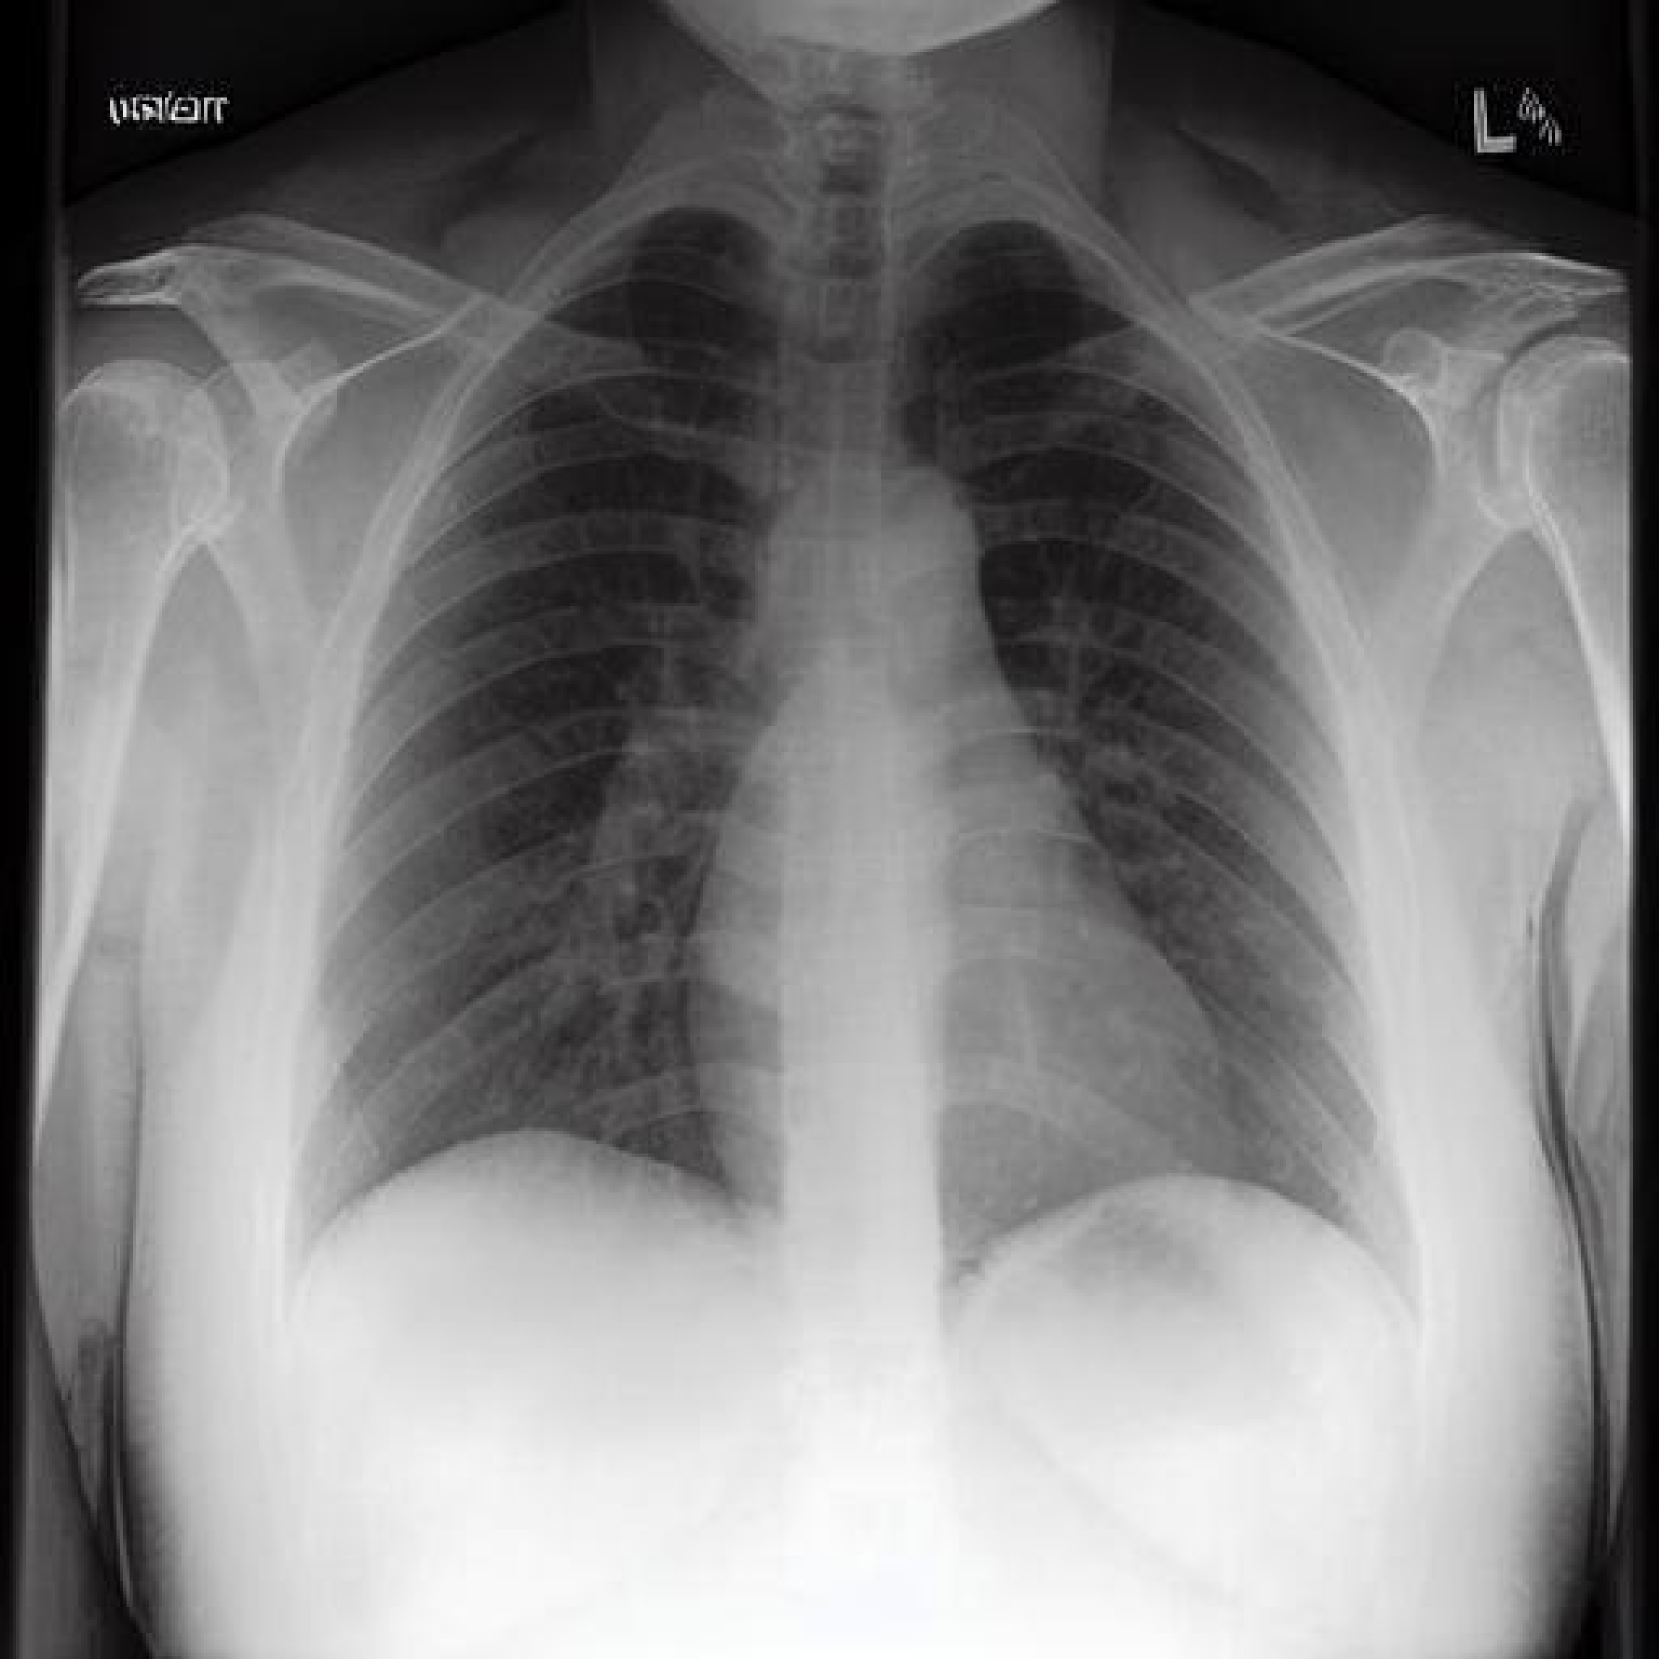

Qualitative Evaluations Our qualitative evaluation demonstrates two primary capabilities of our method: (i) the ability to remove and, for completeness, add medical devices to the original image, and (ii) the ability to emulate distinct visual pathologies of different diseases.

Chest radiographs contain a variety of medical devices [Gambato et al.(2023)Gambato, Scotti, Borsari, Zambon Bertoja, Gabrieli, De Cassai, Cester, Navalesi, Quaia, and Causin] such as chest tubes for draining air, blood, or fluid from the pleural space, surgical clips that are often visible after procedures like axillary node dissection, or pacemakers that regulate heart rhythm, typically seen as a small box near the clavicle [Mathew et al.(2019)Mathew, Alexander, Patel, and Low]. These devices vary in shape, size and position in the X-ray image. Our method, PRISM, can remove medical devices, demonstrating robust performance across various device types and positions without any external classifier-based supervision or image-level mask/annotations.

Refer to caption

Figure 3: Sample pairs of original and CF images demonstrate the capability of PRISM to remove and add medical devices (e.g. wires, pacemaker) in high resolution. Left: CF images with medical devices removed. Language guidance is T𝑇Titalic_T: chest xray of the patient with lots of medical devices, Tsuperscript𝑇T^{\prime}italic_T start_POSTSUPERSCRIPT ′ end_POSTSUPERSCRIPT: chest xray of the patient without medical devices. Note that the baseline method cannot properly remove medical devices; Right: CF images with added medical devices. Language guidance is T𝑇Titalic_T: chest xray of the patient with no support devices, Tsuperscript𝑇T^{\prime}italic_T start_POSTSUPERSCRIPT ′ end_POSTSUPERSCRIPT: chest xray of the patient with lots of support devices.

In Fig. 3, we show how, by using language guidance, we can remove complex medical devices from the given image without altering the pathology of the disease. We also compare our framework to a baseline method, GANterfactual [Mertes et al.(2022)Mertes, Huber, Weitz, Heimerl, and André], a classifier-guided CF generator. This method relies on the gradient from a pre-trained classifier for guidance and fails to remove devices from the image. Next, we evaluate our method’s ability to effectively differentiate between diseases during CF image generation. Specifically, Fig. 4 demonstrates PRISM’s performance in generating CFs for two diseases: Pleural Effusion and Cardiomegaly.